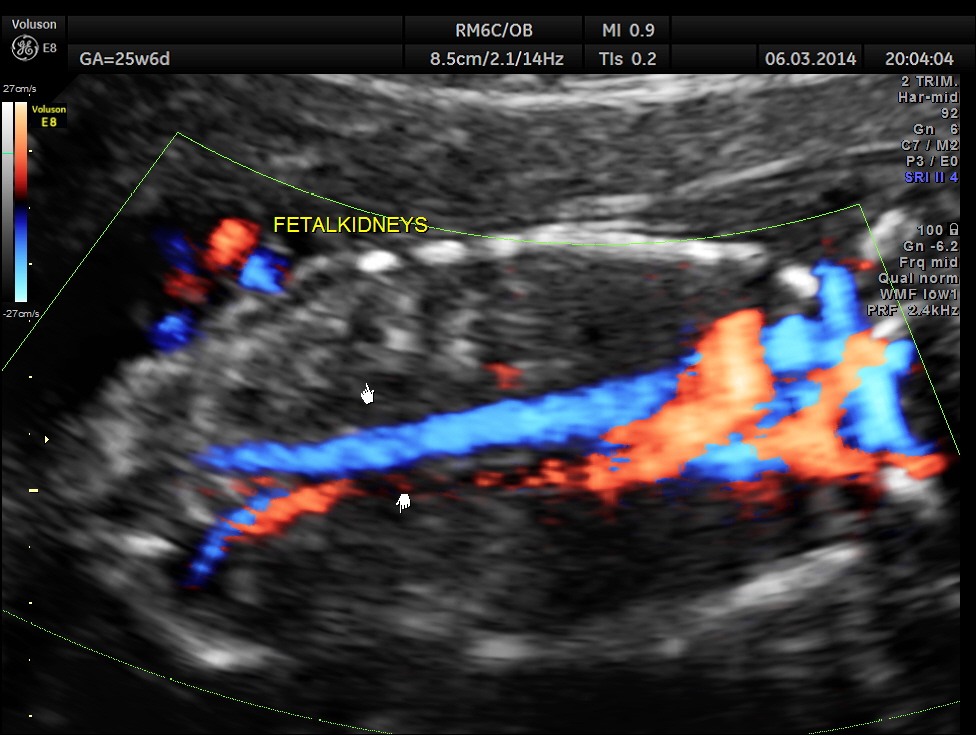

Umbilical arterial P.I. and R.I. are higher for the GA.